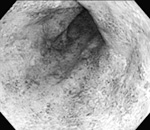

それにたいして潰瘍性大腸炎では食事の影響は比較的少なく、炎症はほぼ大腸だけにおきます。直腸から盲腸方向にむかって連続的に腸の壁全体に浅い潰瘍が多発(下部写真)することが多く、穴があくよりは下痢や粘血便が主となる病気です。

| 内視鏡で見た大腸。右が潰瘍性大腸炎で浅い潰瘍が一面にあり、 荒れている。左は正常な大腸で、血管が透けて見える |